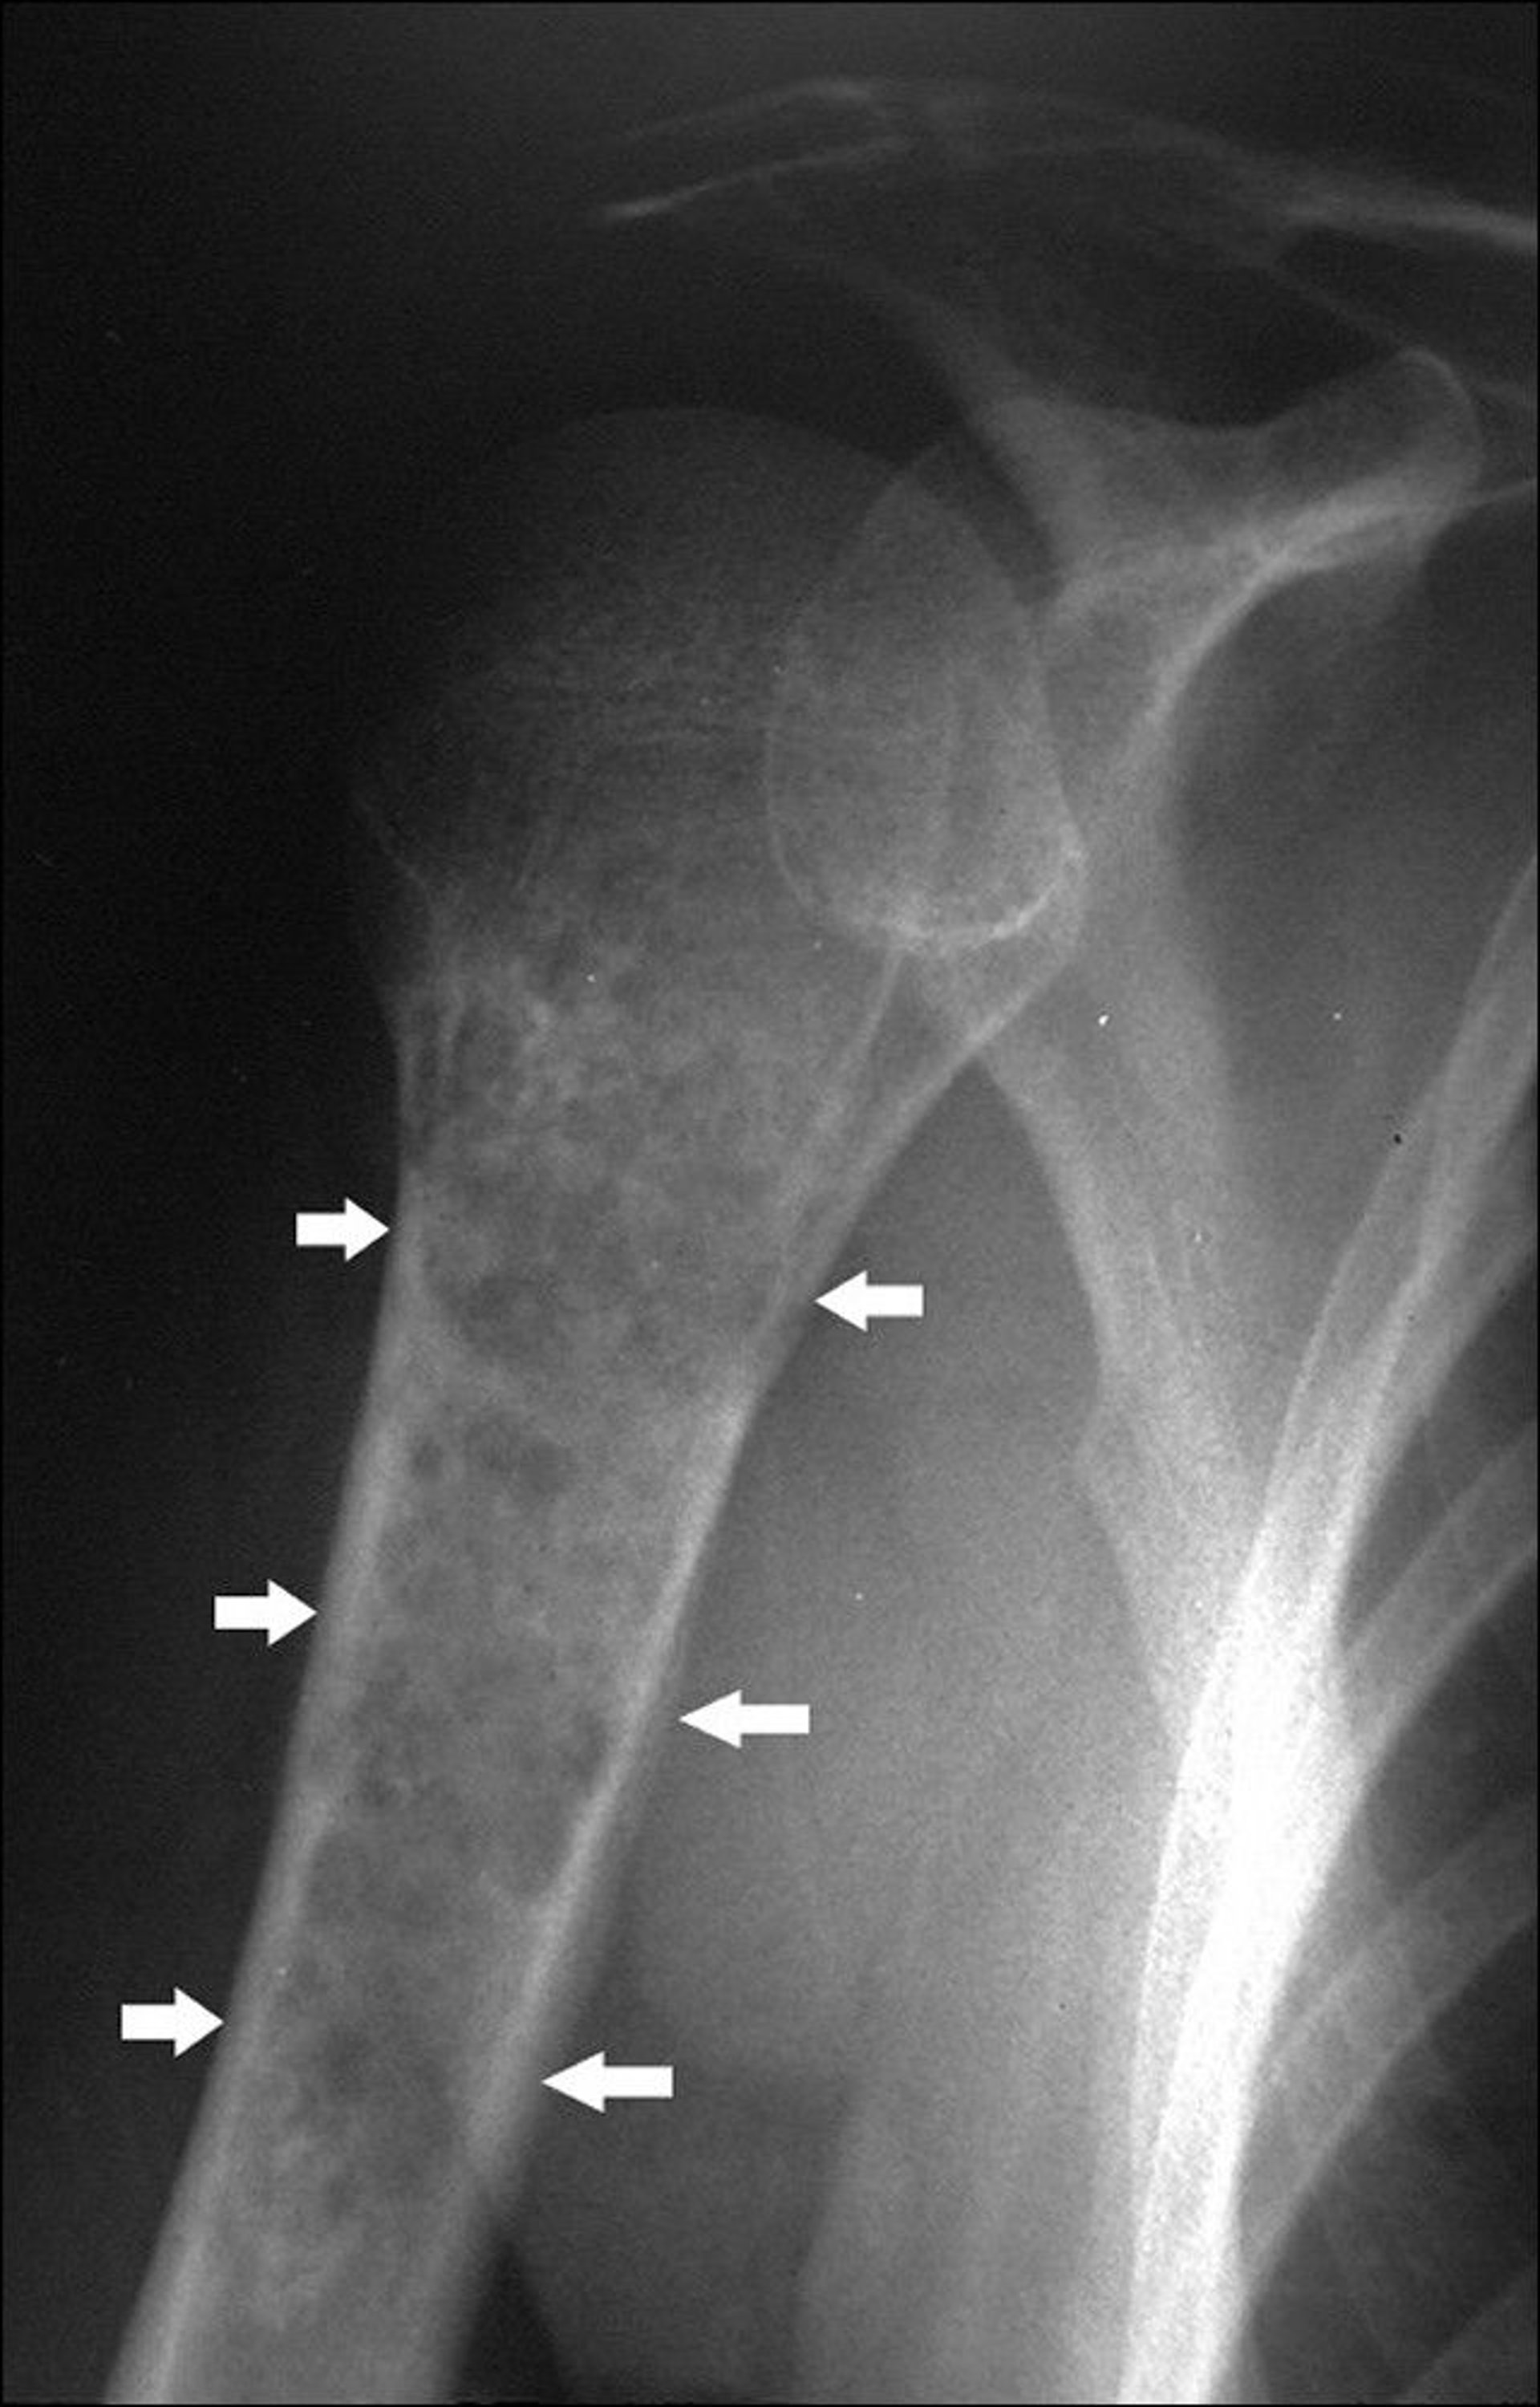

Chondrosarcoma of the Humerus

This shoulder radiograph shows a stippled calcified lesion in the humerus (arrows) with endosteal scalloping, including some areas of destruction through the cortex.

Image courtesy of Michael J. Joyce, MD, and Hakan Ilaslan, MD.